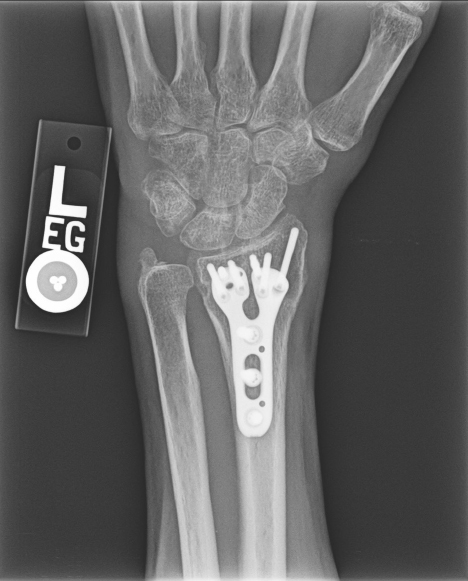

X-rays will be used to confirm the diagnosis. Fortunately, many of these fractures can be treated without surgery. Sometimes, the best thing is to push the fracture back into a better position and then hold it there with a cast. However, there are occasions where surgery is the best option. Surgery allows for the bones to be held in a better position more securely. With surgery, the bones can be held in place with pins, plates, and screws, and sometimes a combination of all of these. No matter the treatment, these fractures usually require at least 6 weeks to heal before it is ok to begin using the hand and wrist without restriction, but it often takes months before the pain and the stiffness fully resolve.

60-year-old female without other medical problems fell and landed primarily on her left hand and wrist. She had immediate pain and deformity at the wrist. She went to the emergency room where x-rays were performed showing her injury – a distal radius fracture. An attempt was made at improving the fracture position by the emergency room doctors and she was splinted. She was then referred to my clinic. She was seen soon afterwards. It was noted on new x-rays that the broken bone was in a less than ideal position. After a thorough discussion of the patient’s goals and concerns, surgery was felt to be the best option for her. Surgery was performed one week after her initial injury under general anesthesia. She was allowed to begin moving her wrist after her first post-operative visit 10 days after surgery and begin full weight bearing on the hand and wrist just under 6 weeks after surgery. She now has full function.